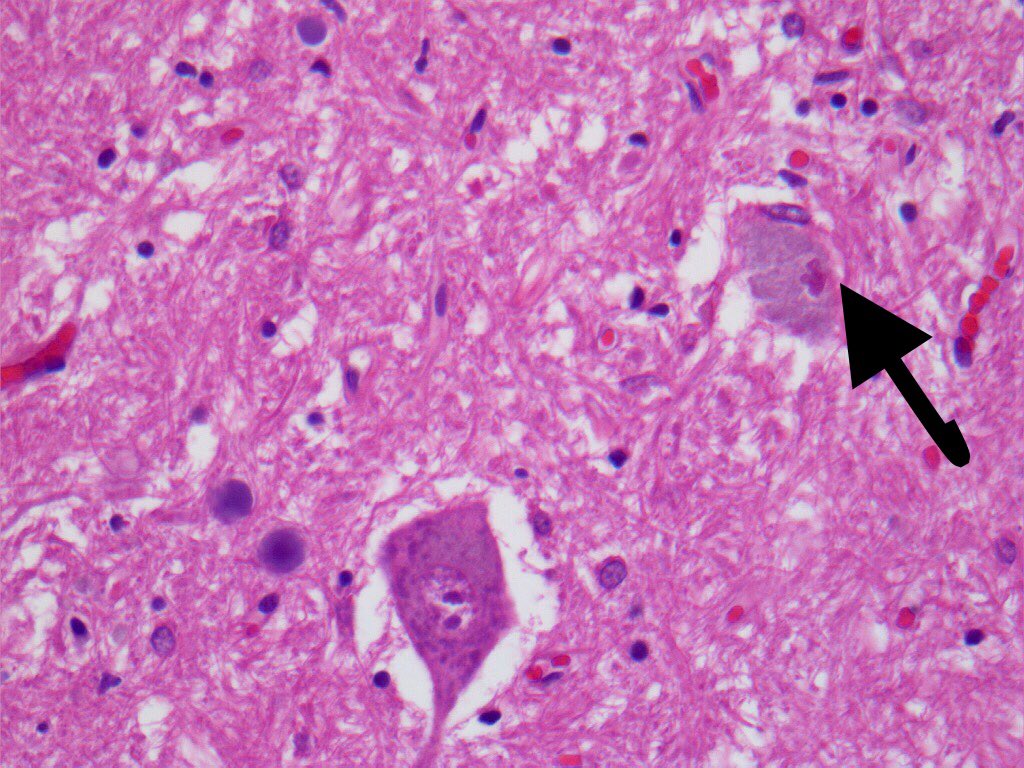

@bansar_bansaria Woo Cheal Cho, MD Bin Xu Sanjay Mukhopadhyay Jerad Gardner, MD Kalyani Bambal Xiaoyin "Sara" Jiang, MD (She/Her) @DrFNA Vijay Shankar S Bunina bodies in motor neurons of the anterior horn in ALS